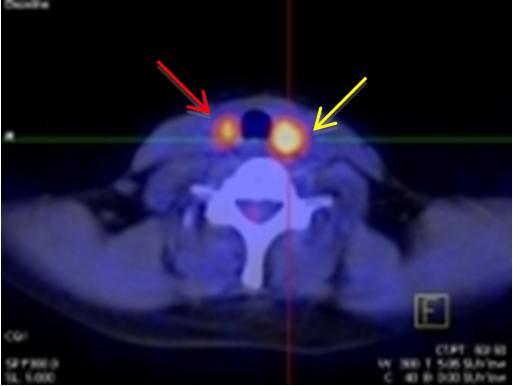

Nhân thùy phải tuyến giáp, kích thước: 1,4x1,0cm tăng hấp thu FDG, maxSUV=5,11. Nhân thùy trái tuyến giáp, kích thước: 1,9x1,6cm tăng hấp thu FDG, maxSUV=6,8.

Hình ảnh nốt kích thước: 1,6x1,2cm vị trí 1/4 dưới trong vú phải

tăng hấp thu FDG, max SUV=2,8.